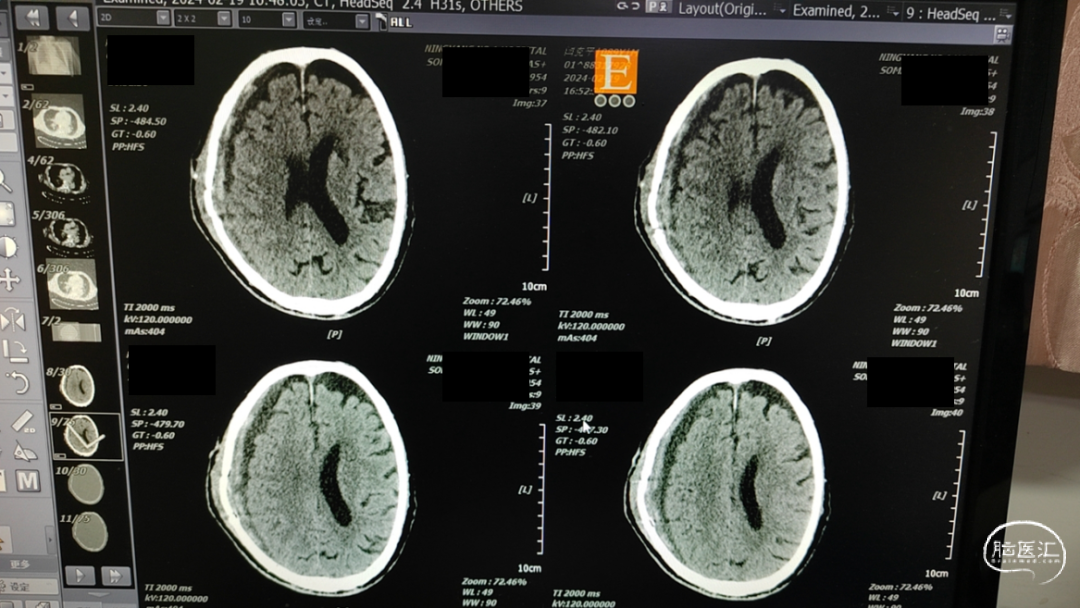

术前CT

![]()